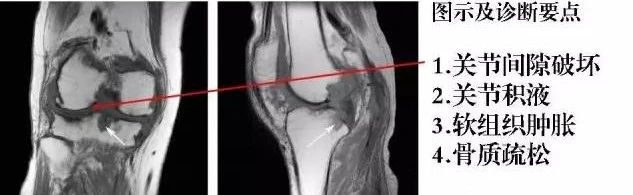

5、神经病性关节:神经病性关节病(neurogenic arthropathy,NA)又称Charcot关节,是由关节本体感觉、痛觉障碍,失去保护性反应,反复遭到损伤而引起的继发性关节病。早期关节红肿、发热,多无疼痛,少数可有持续性疼痛,关节活动时疼痛加剧。晚期由于关节囊和韧带松弛,发生关节半脱位或完全脱位。